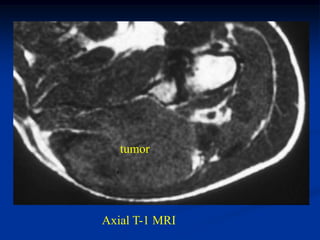

Case #263           Coronal proton density MRI

tumor

72 year female with MFH deltoid muscle

Another proton density coronal cut